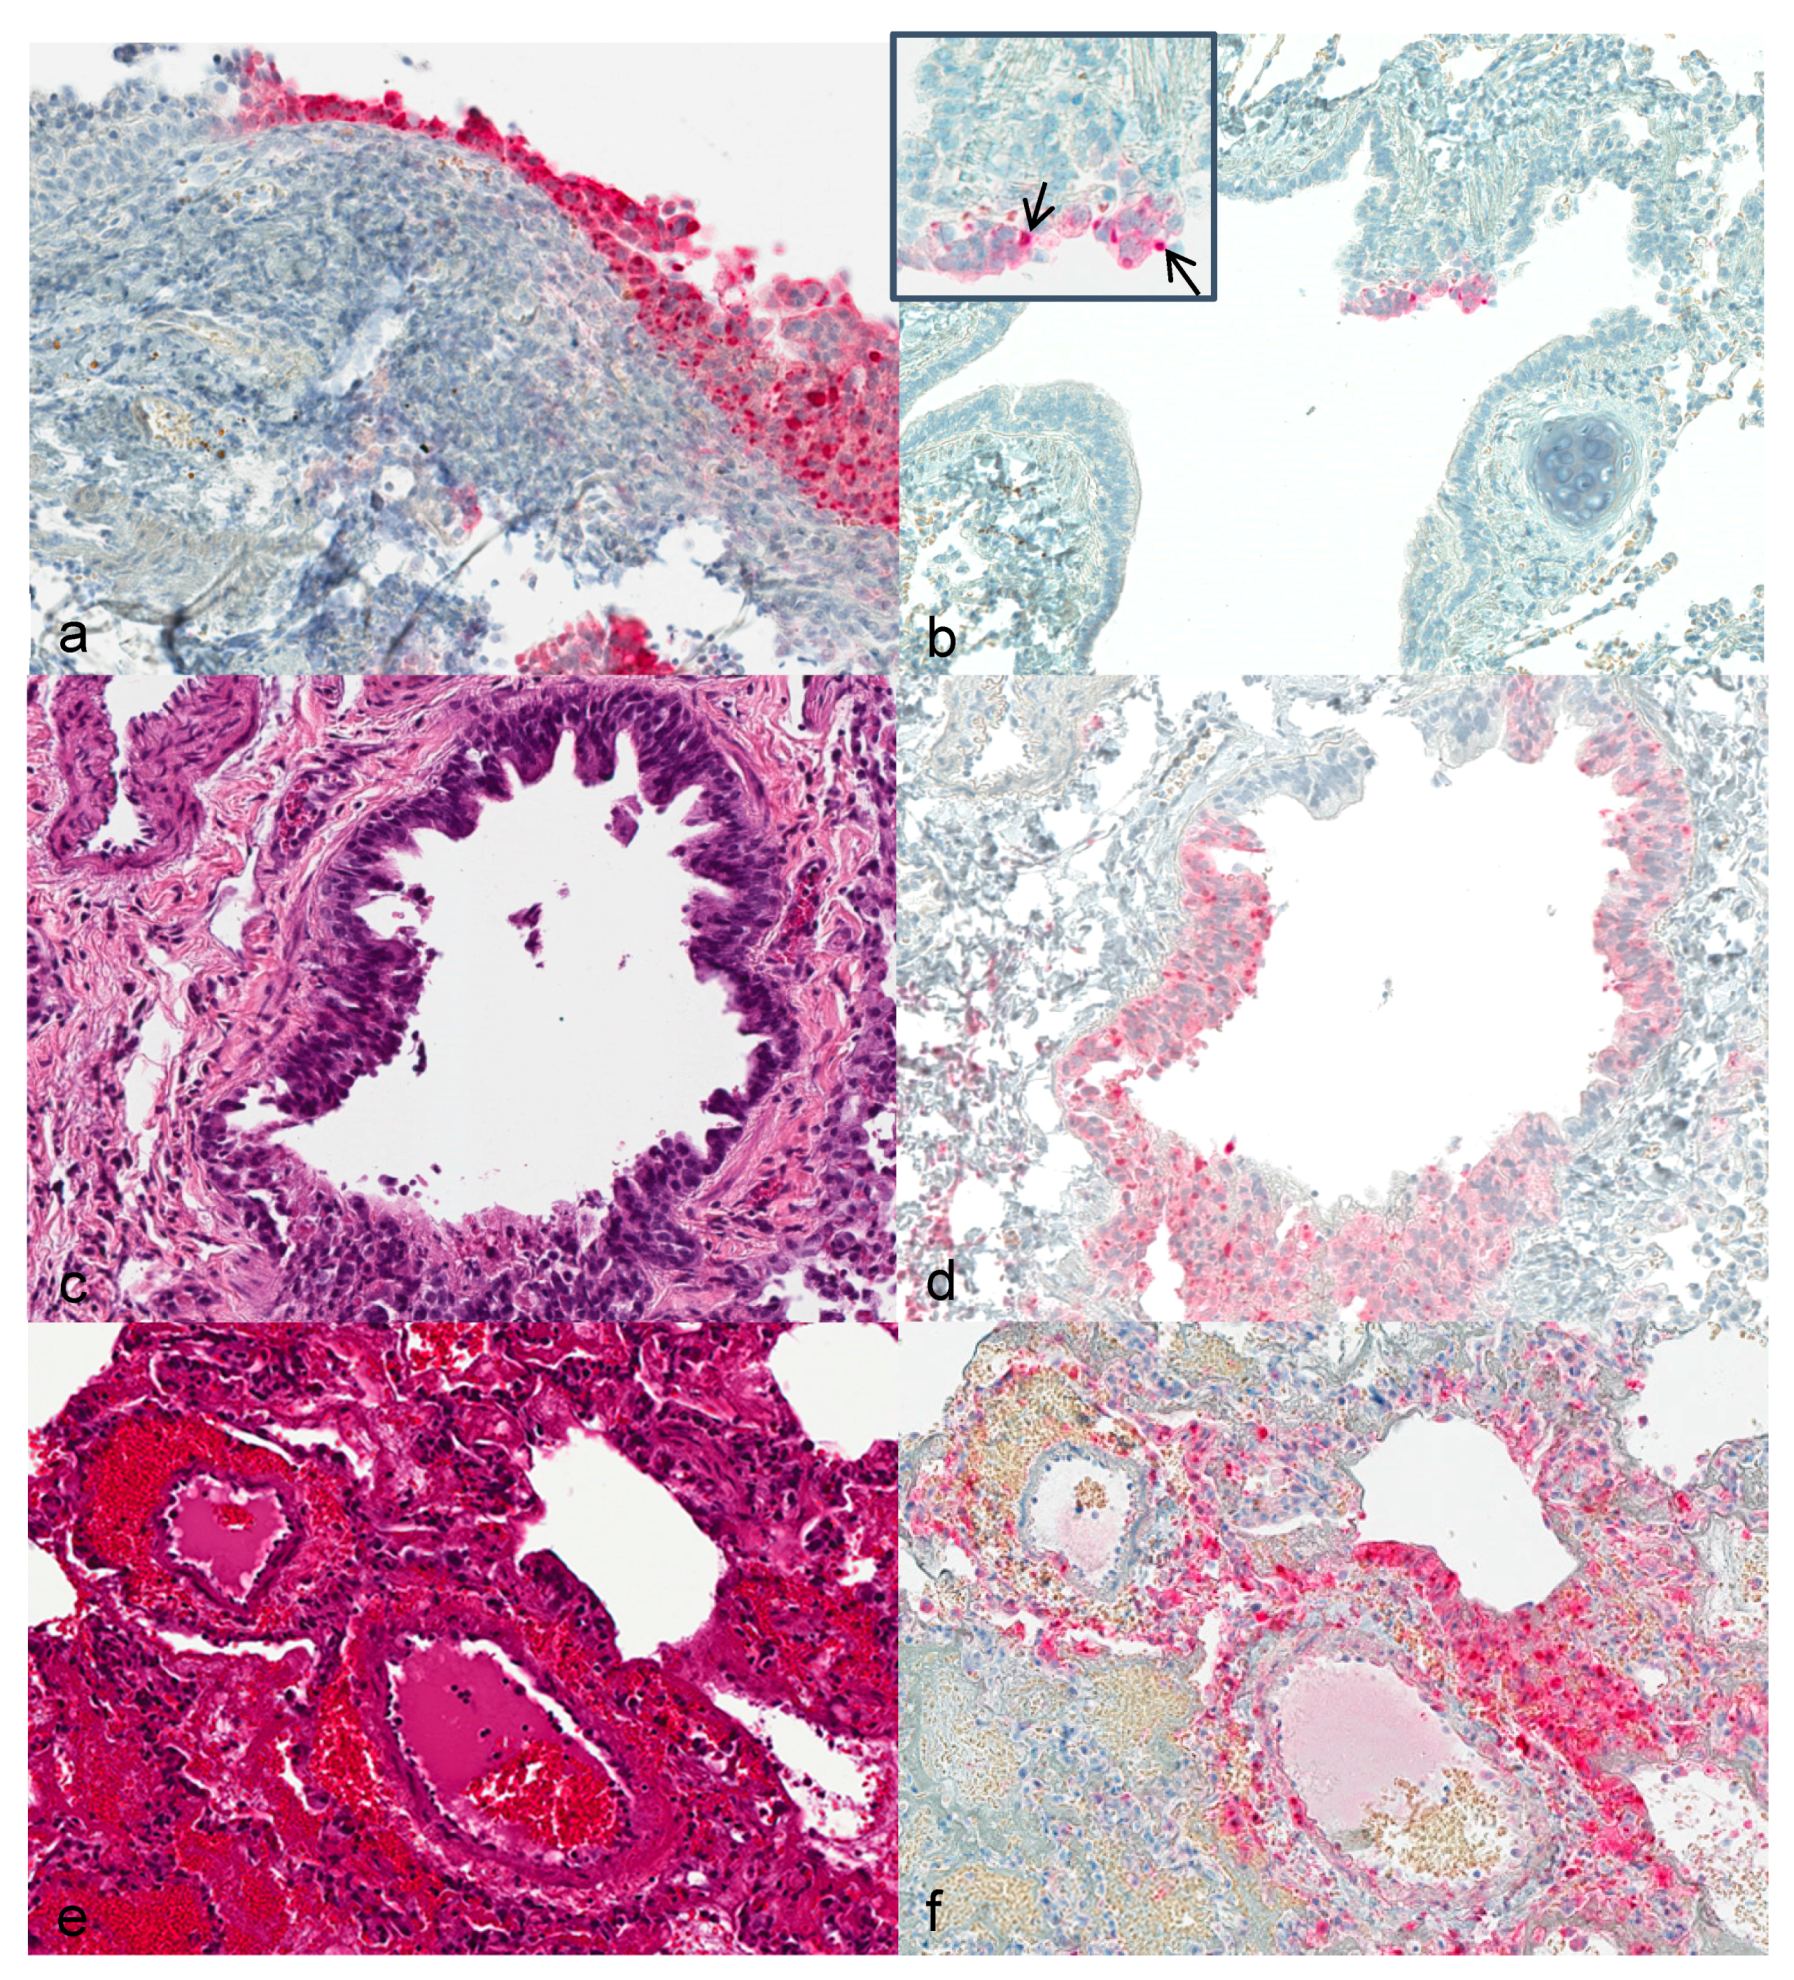

3.3. Histopathology and Immunohistochemistry

3.4. Transmission Electron Microscopy